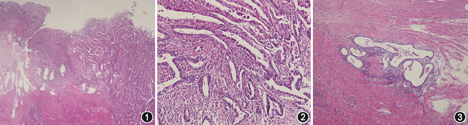

女性,55岁。因"排便习惯改变2年,便血5个月"于2015年10月6日入院。患者2年前无明显诱因出现左下腹阵发性刺痛,伴腹泻、便秘交替,腹泻2~3次/d,感大便控制较差,伴大便不尽感,未予重视。5个月前出现便血,为新鲜血块。患者于当地医院就诊,怀疑直肠肿物。遂就诊于我院,体检未及明显异常,肿瘤标志物检查血CA125略升高(13.7 U/ml),癌胚抗原正常。盆腔超声显示子宫肌层数个低回声,考虑子宫多发肌瘤。胸腹盆CT增强扫描显示直肠乙状结肠交界区局部肠壁偏心性增厚。全程结肠镜检查显示距肛门15 cm乙状结肠与直肠交界处凹陷性病灶,病变大小2 cm×3 cm,表面呈鱼肉样,伴渗血,边缘不规则,边界不清,病变累及管腔周长1/2,内镜尚能通过,组织脆、弹性差;活检病理学结果示纤维组织内异型的腺管样结构浸润性生长,免疫组化示细胞角蛋白(cytokeratin,CK)7(+)、CK20(-)、配对盒基因8(paired box8,PAX-8)(+)、尾型同源盒转录因子2(caudal related homeodomain transcription 2,CDX-2)(-),提示转移性腺癌,源于女性生殖系统。PET-CT显示直肠乙状结肠交界处肠壁增厚、代谢增高,符合恶性病变表现,伴盆腔内淋巴结转移。初步诊断:直肠占位,考虑为转移癌,原发灶待查。患者于2015年10月20日在全身麻醉下行腹腔镜辅助直肠癌前切除术+子宫双附件切除术,术中探查肝、小肠未见异常,肿瘤位于腹膜反折上方,浸透浆膜,与子宫体右下部浸润、粘连;切除病变肠管及子宫双附件,清扫肠系膜下血管根部及直肠上动脉根部淋巴结。术后组织病理学检查显示,切除直肠长8 cm,直肠上段肠壁全层有腺管状腺癌浸润,黏膜破坏、溃疡形成,腺癌与周围正常黏膜未见移行(图1),并有浆膜受侵;肿瘤细胞形成不规则腺管状结构,细胞核圆或椭圆形,核膜厚,核仁清楚(图2);淋巴结转移癌(肠周淋巴结8/25,肠系膜下血管根部及直肠上动脉根部淋巴结0/5);子宫、双侧输卵管及卵巢未见肿瘤。免疫组化结果显示:CK7(+)、CA-125(+)、P16(+)、PAX-8(+)、CDX-2(-)、CK20(-)、雌激素受体(+)、孕激素受体(-)、WT-1(-),提示肿瘤源于女性生殖系统。患者存在区域淋巴结转移,但首次病理学检查结果未能明确原发肿瘤部位,无法制定后续辅助治疗方案,多学科综合治疗团队讨论后建议病理科对肠管标本进行再次切片。第2次病理学检查结果显示:肿瘤远端4 mm处直肠壁浆膜侧肌层内可见小灶子宫内膜异位(图3)。因此,考虑患者直肠腺癌源于异位子宫内膜,形态符合子宫内膜样癌。

不同来源的腺癌,形态学上可能有特征性表现,有助于进行鉴别诊断。如卵巢浆液性癌常见微小乳头状结构,细胞核异型性大,容易有砂粒体样钙化。分化好的结直肠癌细胞呈高柱状,细胞核瘦长深染,肿瘤性腺腔内常见凋亡及坏死。但是,肿瘤分化不是特别好时,许多形态学特点不鲜明,则难以鉴别。本例患者为腺管状结构的腺癌,肿瘤细胞圆或椭圆形,没有特别突出的形态学特点。

在免疫组化确定肿瘤为来源于女性生殖系统的转移癌后,病理科对手术标本进行了再次筛检,最终在肿瘤旁直肠浆膜侧检出小灶子宫内膜异位,考虑肿瘤发源于异位的子宫内膜。子宫内膜异位是常见的女性生殖系统异常,约80%发生于卵巢,21%~24%发生于女性生殖系统外,最常见于直肠、乙状结肠、直肠阴道隔、盆腹膜,也可见于腹壁、脐、胸膜等部位[1]。卵巢异位子宫内膜恶性转化为卵巢癌的学说首先于1925年由Sampson[2]提出,此后的研究结果证实卵巢外的异位子宫内膜同样可以发生恶性转化[3],经过不典型子宫内膜异位,通常转化为子宫内膜样癌或透明细胞癌。不典型子宫内膜异位和子宫内膜样癌可以共同出现9p、11q和22q的杂合性缺失[4]。多种遗传学改变可能与这一转化途径相关,基因包括8-氧鸟嘌呤脱氧核苷、PTEN、p53、ARID1A、MLH1、bcl-2、KRAS等;子宫内膜异位灶较大、高雌激素、肥胖等是发生子宫内膜异位相关癌的危险因素[5]。